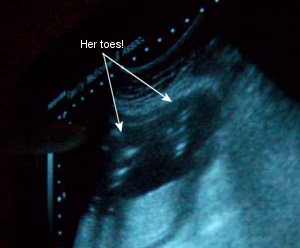

November 26th: I only gained 1 pound in two weeks, so I was now 138. She’s measuring well and my glucose was fine. I asked again to check if she’s a girl (yes, I won’t believe it till I see it!), but her little legs were too tightly crossed together. I did, however, get to see her spine and toes! Oh, and she’s already turned upside down! The earliest of all the kids (the other 3 turned over at exactly 28 weeks).

Sono Pic: